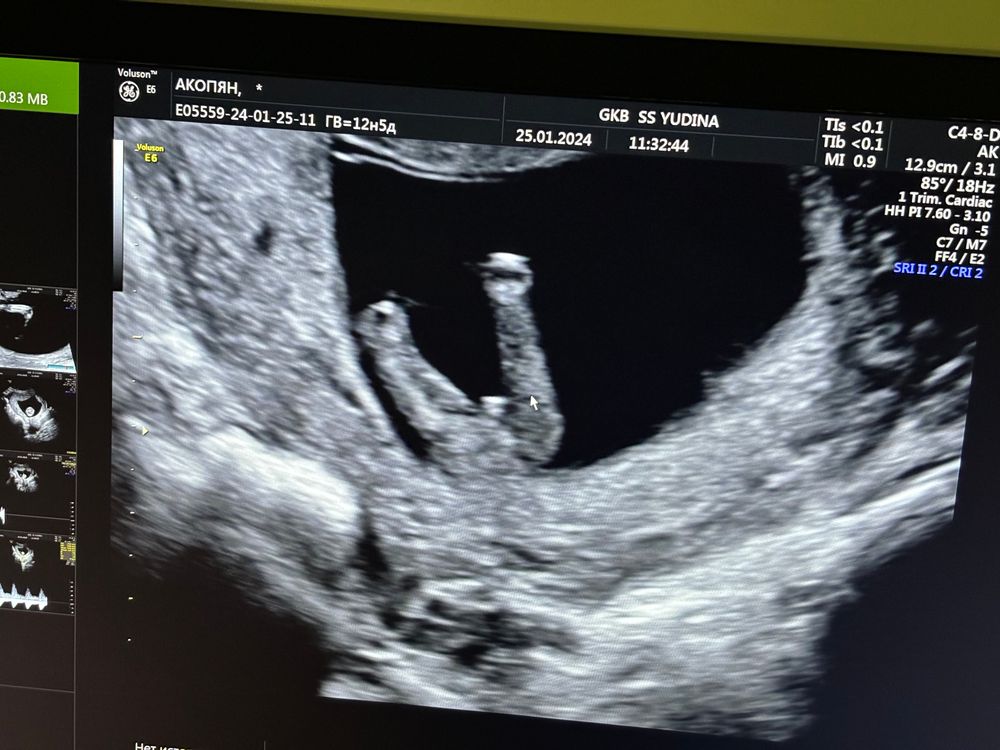

Сходила сегодня на Первый скрининг очень переживала , но малышка хорошо растет соответствует своему сроку , отклонений не каких нет прекреплена по задней стенке матки , сердечко 164 ударов в минуту , и сказали что предположительно будет девочка , очень обрадовалась так как предчувствие было да и хотели дочку проводила скрининг в род доме Юдина и врач сказал больше похоже на половые губки что на мальчишеского нет намека ))) ну что доченька ждем тебя всей большой нашей семьей ❤️❤️ расти и набирайся сил